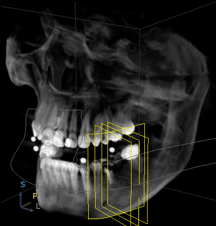

Innovative, strahlungsärmere und äußerst präzise 3D-Röntgentechnik: DVT

Vor manchen Eingriffen wird ein Computertomogramm (CT) benötigt. Ein CT ist aber aufwendig, teuer und die Strahlenbelastung ist hoch. Da jedoch außerdem mit der herkömmlichen 2D-Röntgentechnik etwa 20 Prozent aller krankhaften Befunde im Zahn-, Mund- und Kieferbereich kaum oder nicht zu erkennen sind, haben wir uns dazu entschlossen, neue Technologien im Rahmen der dreidimensionalen Digitalen Volumentomografie (DVT) für Ihre Sicherheit und Gesundheit einzu - setzen.

Kürzere Untersuchungszeiten bei schnellerer Leistung, weniger Strahlenbelastung und maximaler Bilddarstellung zeigen deutlich die Innovation, die wir für Ihren Nutzen einsetzen. Diese Schnittbilder kann unser Hochleistungsrechner zu einem dreidimensionalen, digitalen Datensatz verarbeiten, aus dem wir nach der Untersuchung auf dem Monitor die 3D-Ansicht Ihres Kiefers in jeder beliebigen Ebene rekonstruieren können. Wir als Ihre Behandler erhalten dadurch detaillierte 3D-Einblicke in Regionen und aus Blickwinkeln, die mit der herkömmlichen zweidimensionalen Röntgentechnik nicht möglich sind.